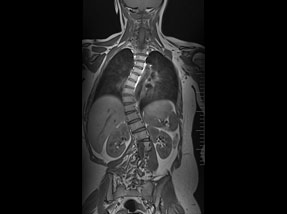

• Pre-Surgery

• Post Surgery

Case 1